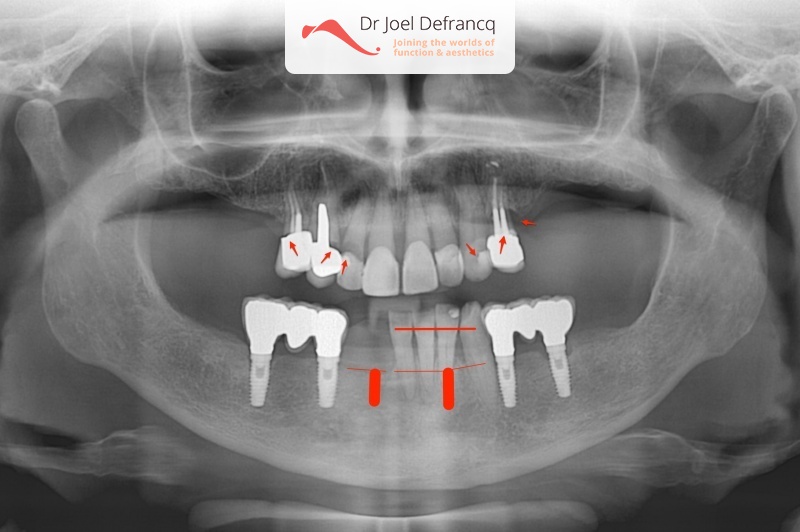

Benedicte: Dentale implantaten en onmiddellijke belasting

Dentale diagnose

- Klasse II divisie 1

Behandeling tandheelkundige implantaten

- Vaste tanden op implantaten (bovenkaak)

- Vaste tanden op implantaten (onderkaak)